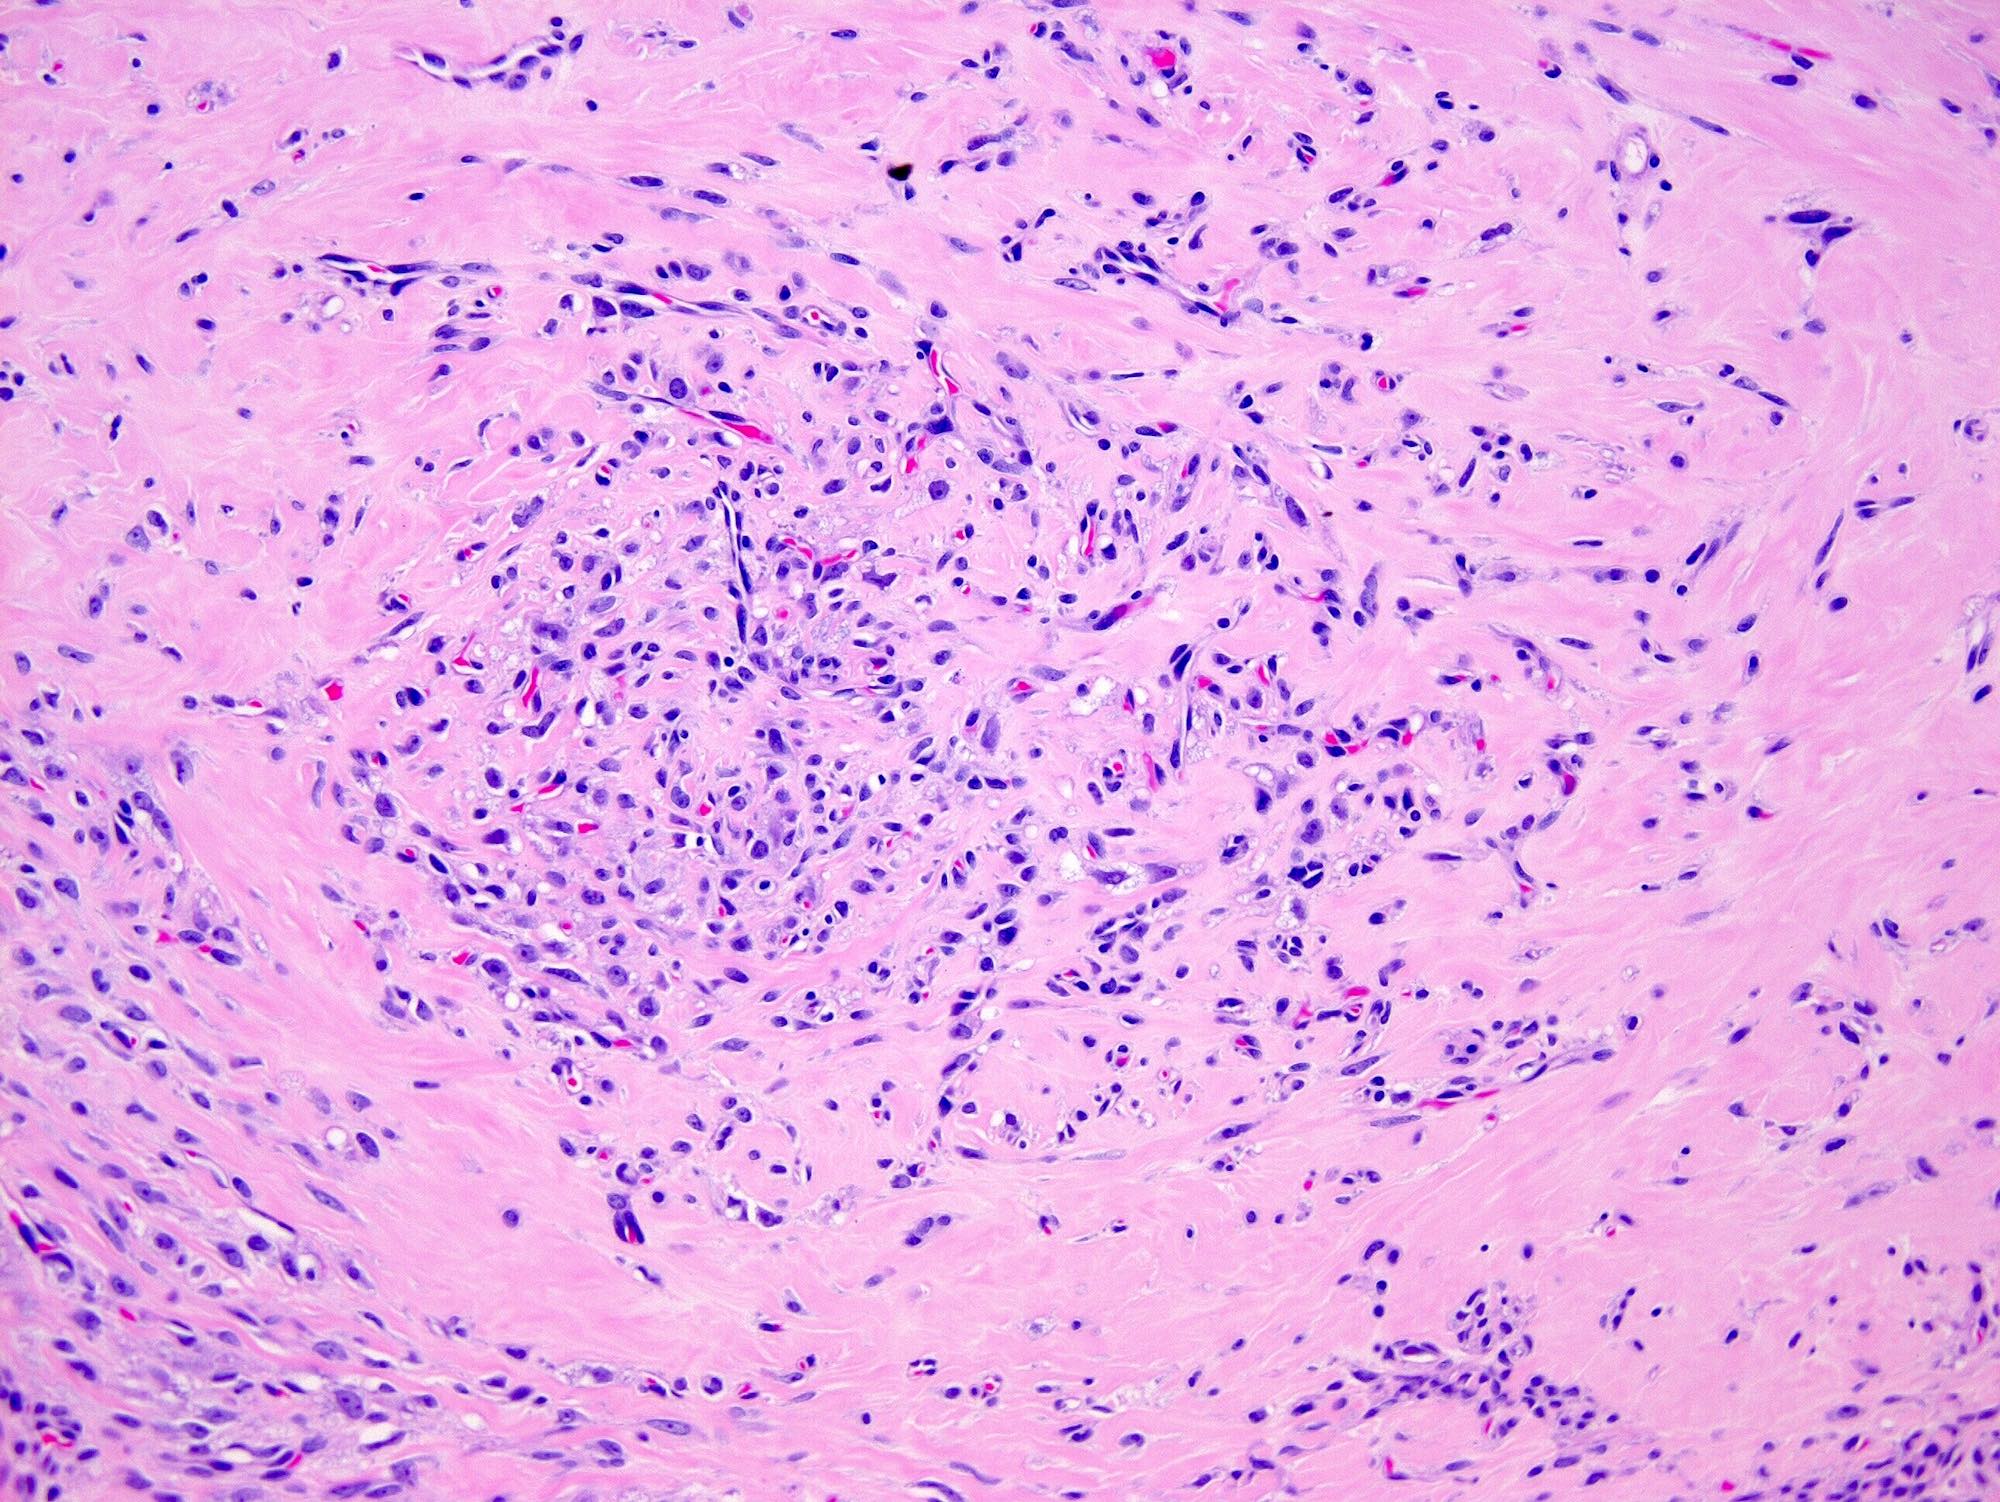

- Alternating cellular and hypocellular areas impart a pseudolobular appearance

- Thin, dilated and branching hemangiopericytoma-like vasculature is often conspicuous in both components

- Hypocellular areas can be edematous, collagenous (variably keloid-like) or myxoid

- References: Cancer 1973;31:664, Histopathology 2022;80:360

Microscopic (histologic) images